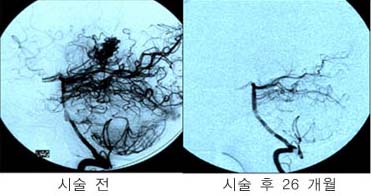

<ÇãÇ÷¼º

³úÁ¹Áß>

ÁÂÃø

Áß³úµ¿¸ÆÀÇ Æó»öÀ¸·Î ÀÎÇÑ ³ú°æ»ö¼Ò°ß(Ç÷°üÁ¶¿µ¼ú»ó

Áß³úµ¿¸ÆÀÌ º¸ÀÌÁö ¾Ê°í ÀÖ´Ù)

<°íÇ÷¾Ð¼º

³úÃâÇ÷>

<¼ö¼ú

Àü> <¼ö¼ú

ÈÄ>

¿ìÃø

Çǰ¢ºÎ ÃâÇ÷ȯÀÚÀÇ ³úCT¼Ò°ß(¼ö¼úÈÄ Ç÷Á¾ÀÌ

Á¦°ÅµÇ¾îÀÖ´Ù)

<³úÁöÁÖ¸·ÇÏÃâÇ÷>

Àü>

³úµ¿¸Æ·ù¿¡

ÀÇÇÑ ÁöÁÖ¸·ÇÏÃâÇ÷ÀÇ CT¼Ò°ß ¹× Ç÷°üÁ¶¿µ¼ú¿¡¼

Àü±³Å뵿¸Æ¿¡ µ¿¸Æ·ù°¡ º¸À̰í ÀÖ´Ù.

Àå¸é> <¼ö¼ú

¼ö¼ú

ÈÄ µ¿¸Æ·ù°¡ º¸ÀÌÁö ¾ÊÀ¸¸ç µ¿¸Æ·ù °æºÎ¿¡

Ŭ¸³ÀÌ µé¾î°¡ ÀÖ´Â °ÍÀÌ º¸À̰í

ÀÖ´Ù.

<³úÁ¤µ¿¸Æ±âÇü>

½Ã»óµ¿

ÀÎÁ¢ºÎ ºÎÀ§ÀÇ ³úÁ¤µ¿¸Æ±âÇüÀÇ MRI¿Í Ç÷°üÁ¶¿µ¼ú

¼Ò°ß

<¸ð¾ß¸ð¾ßº´(¼Ò¾ÆÁßdz)>

³»°æµ¿¸ÆÀÇ Æó»ö¼Ò°ß°ú °æµ¿¸ÆºÎÀ§ÀÇ

ÀÌ»óÇ÷°ü¸Á ¼Ò°ßÀÌ º¸À̰í ÀÖ´Ù. |